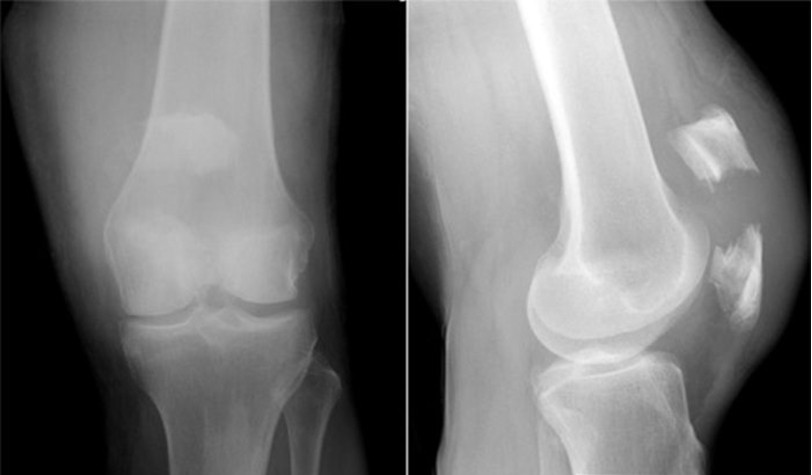

Выбор метода лечения основывается на результатах рентгеновских снимков, компьютерной или магнитно-резонансной томографии. Врач-травматолог анализирует характер травмы, определяет наличие и степень смещения костных фрагментов. На основе этого он решает, применять ли консервативную терапию или хирургическое вмешательство.